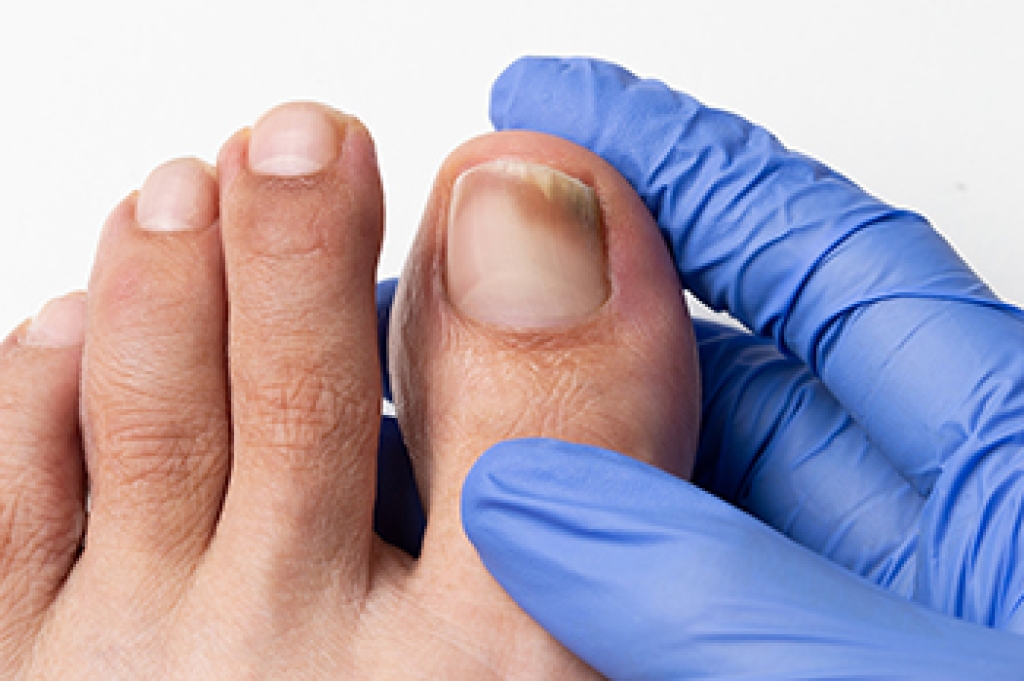

Pickleball, a popular sport combining elements of tennis, badminton, and table tennis, has gained a dedicated following in recent years. However, like any physical activity, it carries the risk of injuries, and one of the most common being plantar fasciitis. This is a painful condition characterized by inflammation of the plantar fascia, which is a thick band of tissue running along the bottom of the foot. The repetitive motions, quick lateral movements, and sudden stops and starts in pickleball can put immense strain on the plantar fascia. Over time, this strain can lead to tiny tears in the tissue, resulting in pain and discomfort, often most pronounced in the heel. Preventing plantar fasciitis in pickleball involves practicing proper warm-up routines, wearing appropriate footwear, and performing regular calf and Achilles tendon stretches. If injury strikes, resting and taking anti-inflammatory medications may help alleviate symptoms. Seeking professional guidance from a podiatrist is crucial for a tailored recovery plan, which may include exercises to strengthen the foot and improve biomechanics. By being proactive about injury prevention and prompt treatment, pickleball enthusiasts can continue enjoying this fun sport while minimizing the risk of plantar fasciitis and other common injuries. If you have heel pain from playing pickleball, it is suggested that you confer with a podiatrist who can offer you additional relief and treatment methods.

Foot and ankle injuries are a common occurrence when it comes to athletes of any sport. While many athletes dismiss the initial aches and pains, the truth is that ignoring potential foot and ankle injuries can lead to serious problems. As athletes continue to place pressure and strain the area further, a mild injury can turn into something as serious as a rupture and may lead to a permanent disability. There are many factors that contribute to sports related foot and ankle injuries, which include failure to warm up properly, not providing support or wearing bad footwear. Common injuries and conditions athletes face, including:

Sports related injuries are commonly treated using the RICE method. This includes rest, applying ice to the injured area, compression and elevating the ankle. More serious sprains and injuries may require surgery, which could include arthroscopic and reconstructive surgery. Rehabilitation and therapy may also be required in order to get any recovering athlete to become fully functional again. Any unusual aches and pains an athlete sustains must be evaluated by a licensed, reputable medical professional.